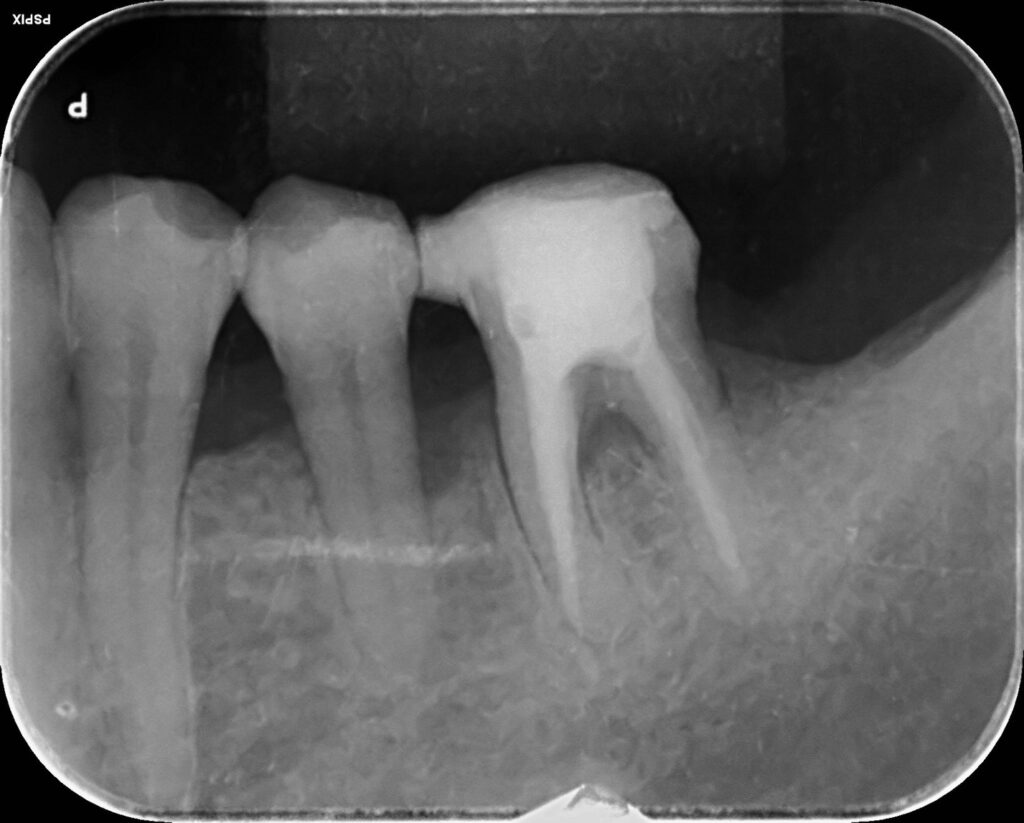

- 精密な検査(ポケット検査・レントゲン・CTなど)

- 歯周病専門的な診断

- マイクロスコープでの状態把握